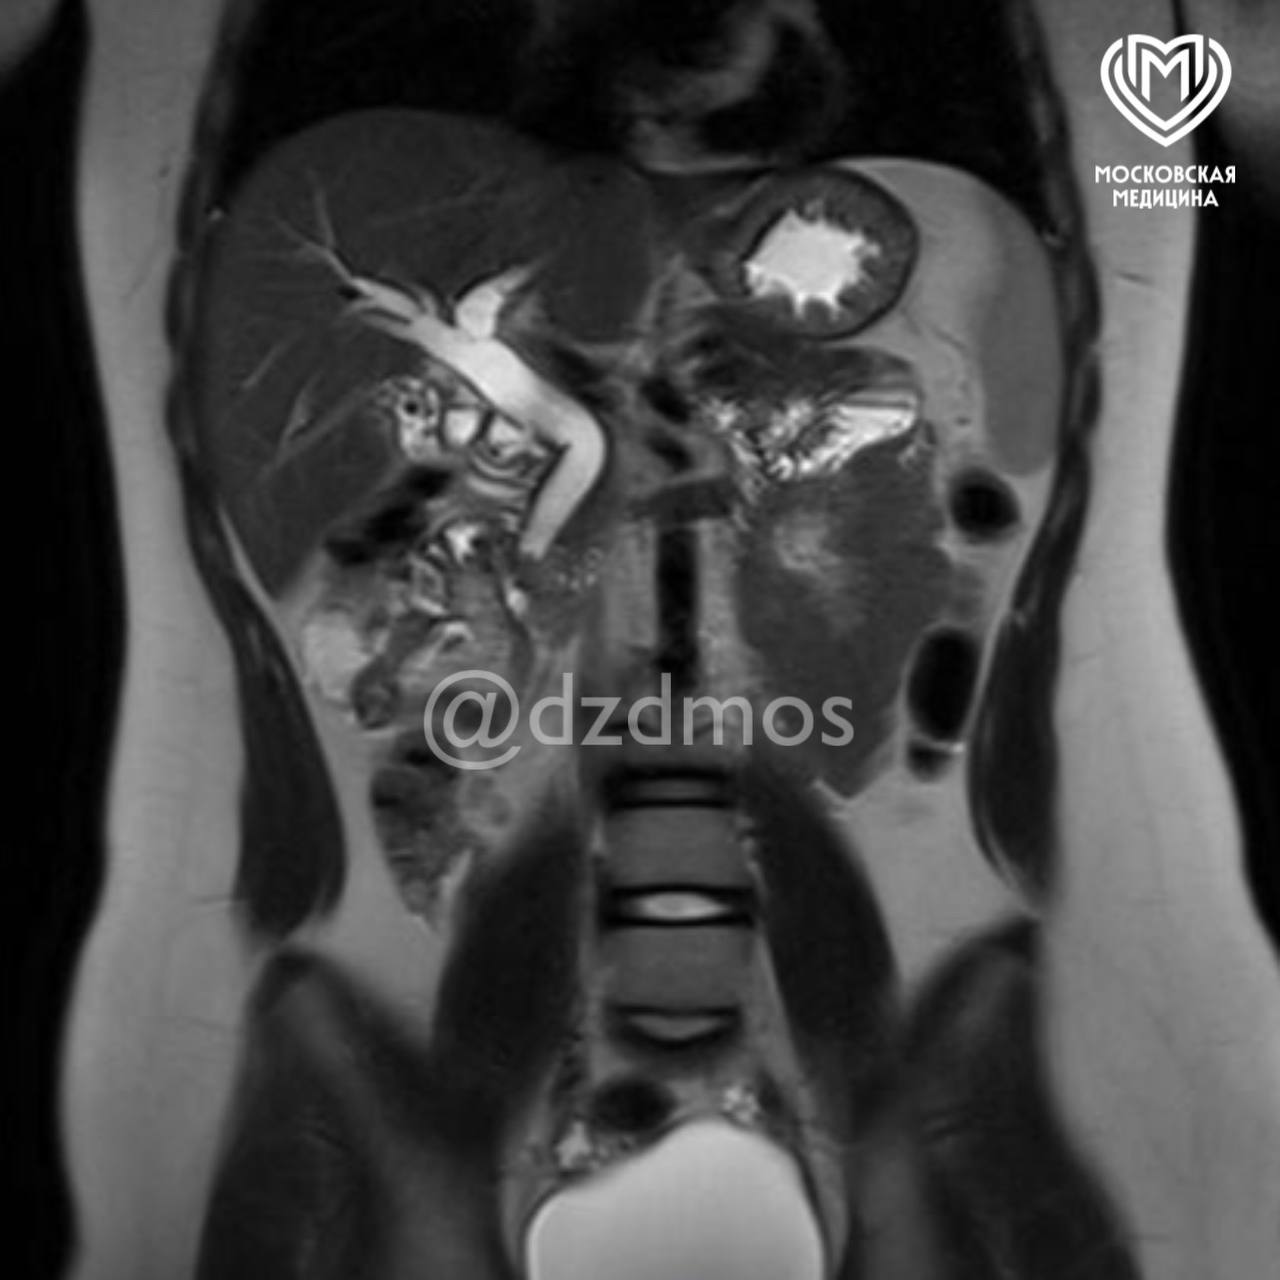

Ребенок поступил в медицинское учреждение с болями в животе, рвотой и общей слабостью. Обследование показало, что в желчном пузыре ребенка скопилось огромное количество камней диаметром до 3 мм. Один из них перекрыл общий желчный проток, что угрожало жизни девочки.

Медики пояснили, что застрявшие в общем желчном протоке камни вызывают нарушение оттока желчи из печени — это приводит к развитию желтухи, начинает страдать печень, как и в случае с юной пациенткой. В тяжелых формах, как отметили специалисты, может развиться воспаление поджелудочной железы.

«Ребенку сделали эндоскопическую папиллосфинктеротомию: специальным аппаратом рассекли сосочек, впадающий в желчный проток, расширили его мышечное кольцо и извлекли камень. Вторым этапом удалили желчный пузырь, полностью забитый камнями», — рассказали в пресс-службе депздрава.